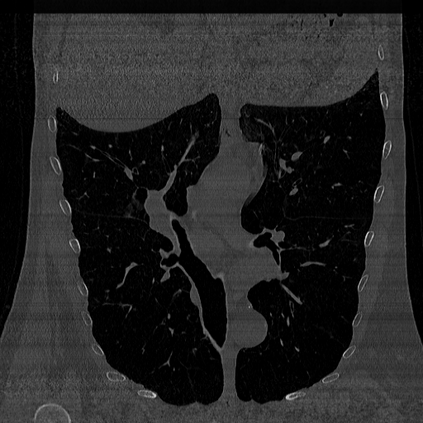

CT reconstruction provides radiologists with images for diagnosis and treatment, yet current deep learning methods are typically limited to specific anatomies and datasets, hindering generalization ability to unseen anatomies and lesions. To address this, we introduce the Multi-Organ medical image REconstruction (MORE) dataset, comprising CT scans across 9 diverse anatomies with 15 lesion types. This dataset serves two key purposes: (1) enabling robust training of deep learning models on extensive, heterogeneous data, and (2) facilitating rigorous evaluation of model generalization for CT reconstruction. We further establish a strong baseline solution that outperforms prior approaches under these challenging conditions. Our results demonstrate that: (1) a comprehensive dataset helps improve the generalization capability of models, and (2) optimization-based methods offer enhanced robustness for unseen anatomies. The MORE dataset is freely accessible under CC-BY-NC 4.0 at our project page https://more-med.github.io/